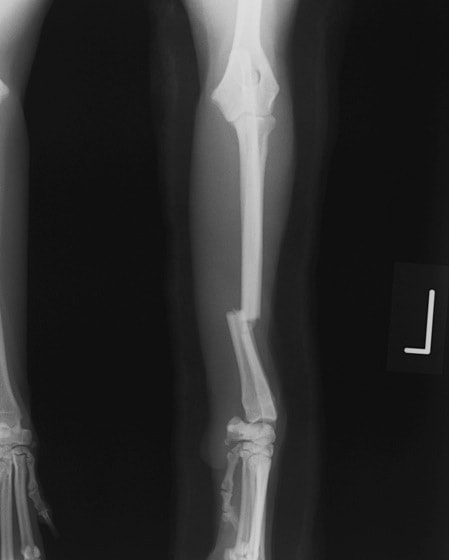

橈尺骨骨折 : 症例1 | 症例2 | 症例3 | 症例4 | 症例5 | 症例6 | 症例7

: 症例8 | 症例9 | 症例10 | 症例11 | 症例12 | 症例13 | 症例14

: 症例15 | 症例16 | 症例17 | 症例18 | 症例19 | 症例20 | 症例21

トイプードル 右遠位橈尺骨短斜骨折のALPSによる内固定